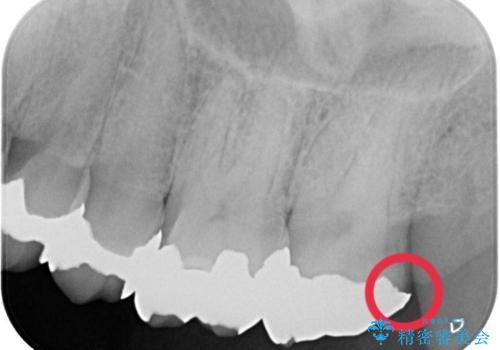

- 主訴:詰め物と歯の境目に穴が空いているとクリーニング時衛生士から指摘された。

保険適用のメタルインレーと歯質の境目にう窩ができており、補綴物のやり替えとなりなした。

メタルインレーを除去したところう窩が深く、遠心の健歯質が歯肉縁下深くに位置したためディスタルウェッジ術を行い骨と歯肉の高さを下げた上で補綴しています。